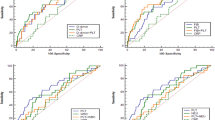

Dynamic changes in PLT indices

PTC, MPV, and PDW values were measured at all time points to dynamically monitor the activation of PLT. As shown in Fig. 2, MPV/PTC and PDW values were significantly higher at T3-T5 than at T1(P < 0.05). Meanwhile, MPV/PTC and PDW values were remarkably greater in the dissection group than in the SO group at T3-T5 (P < 0.05). These data indicated that PLT were activated at 2 h after the operation, and reached a peak at 4 h after the operation.

Dynamic changes in MPV/PTC and PDW. a MPV/PTC value was significantly greater at T3-T5 than at T1 (P < 0.05). It was also remarkably higher at T3-T5 in the dissection group than in the SO group (P < 0.05). b PDW value was significantly higher at T3-T5 than at T1 (P < 0.05). It was also remarkably higher at T3-T5 in the dissection group than in the SO group (P < 0.05)

Dynamic changes in plasma inflammatory cytokines

TNF-α and IL-6 were chosen to represent systemic inflammatory status. Interestingly, after the T2 time point, both TNF-α and IL-6 in the dissection group significantly climbed, and reached highest levels at T5 (P < 0.05, Fig. 3a). Similar to the changes in PLT indices, both TNF-α and IL-6 at T3-T5 in the dissection group were significantly higher than in the SO group (P < 0.05, Fig. 3a). Given these patterns, which were similar to the PLT indices, the data strongly suggested that systemic inflammation was present2 h after the operation; there was a close relationship between the activation of PLT and the initiation of systemic inflammation.

Dynamic changes in TNF-α and IL-6. a TNF-α level was significantly higher at T3-T5 than at T1, and was also remarkably higher at T3-T5 in the dissection group than in the SO group (P < 0.05). b IL-6 level was significantly higher at T3-T5 than at T1 (P < 0.05), and was also remarkably higher at T3-T5 in the dissection group than in the SO group (P < 0.05)

Correlations between PLT indices and inflammatory cytokines

To define the relationship between the activation of PLT and the initiation of systemic inflammation, bivariate analysis was used. We studied the correlations between peak MPV/PTC and PDW levels, and inflammatory cytokines at T4. Unsurprisingly, positive correlations between peak MPV/PTC and both TNF-α (r = 0.826, P = 0.011, Fig. 4a) and IL-6 (r = 0.806, P = 0.016, Fig. 4b) were confirmed and are shown in Fig. 4. However, although there were still rough but positive correlations between peak PDW and both TNF-α (r = 0.623, P = 0.082) and IL-6 (r = 0.603, P = 0.069), there were no statistically significant differencesto explain these data.